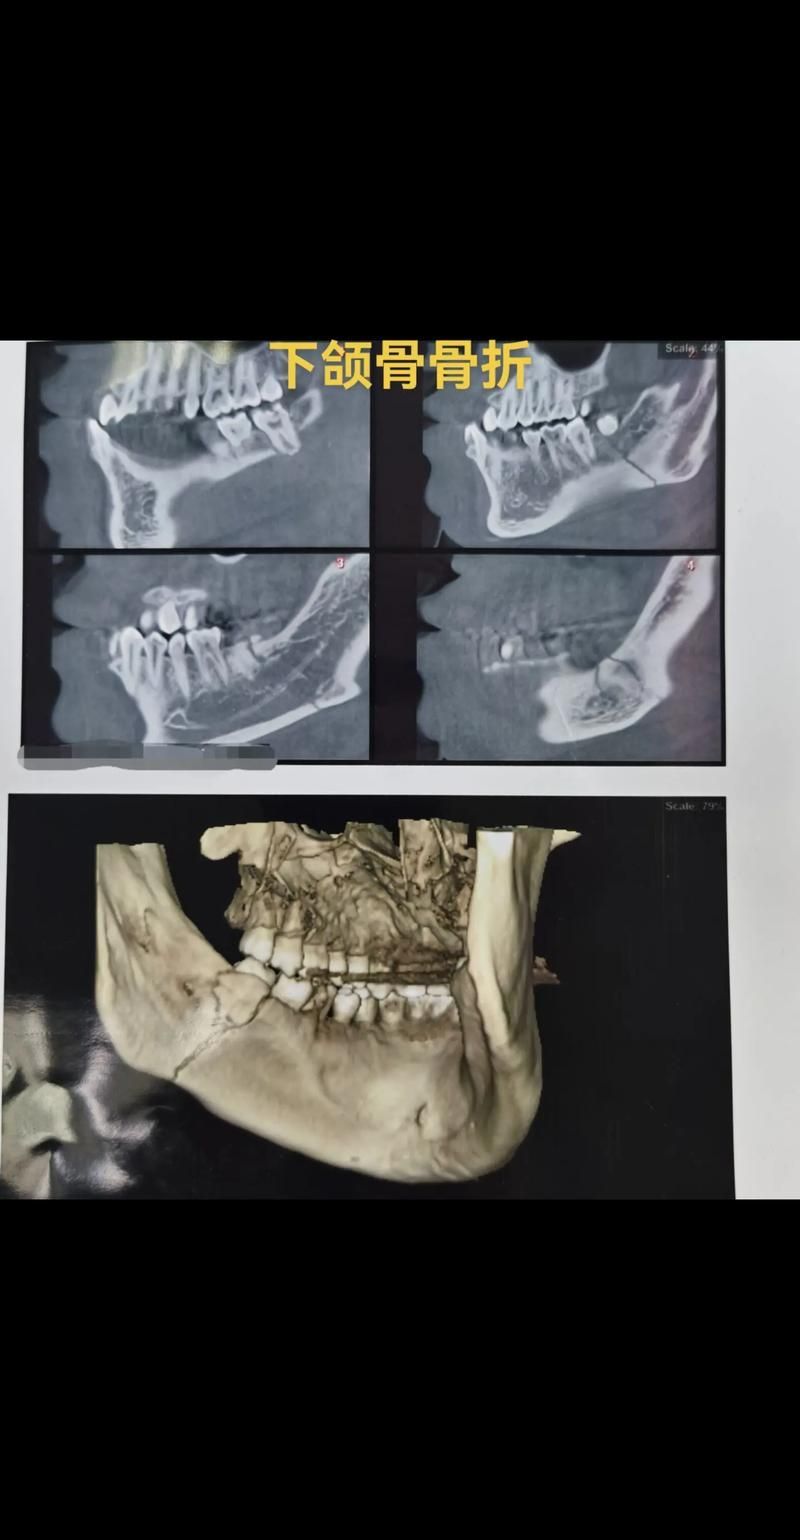

龍魚百科 如何判斷龍魚下頜是否骨折?(如何判斷龍魚(arowana)下頜是否骨折) 魚(Arowana)下頜骨折的診斷通常需要專業(yè)的獸醫(yī)進(jìn)行,以下是一些可能用于判斷龍魚下頜是否骨折的步驟和指標(biāo):,1.觀察外觀:檢查龍魚的口腔和下頜區(qū)域是否有腫脹、淤血或異常的顏色變化。,2.觸摸檢查:輕輕觸摸下頜... 2026-02-19 8 閱讀 7 評(píng)論 楊凌魚缸定做

如何判斷龍魚下頜是否骨折?(真實(shí)龍魚下頜骨折的診斷通常需要專業(yè)的獸醫(yī)雖非直接對(duì)比圖)) 魚下頜骨折的診斷通常需要專業(yè)的獸醫(yī)進(jìn)行,以下是一些可能表明龍魚下頜骨折的跡象:,1.**外觀檢查**:仔細(xì)觀察龍魚的口腔和下頜區(qū)域,骨折可能導(dǎo)致下頜骨變形、腫脹或顏色改變。,2.**行為觀察**:如果龍魚表現(xiàn)... 2026-02-13 8 閱讀 7 評(píng)論 淮北花鳥(niǎo)魚蟲(chóng)市場(chǎng) 龍魚百科